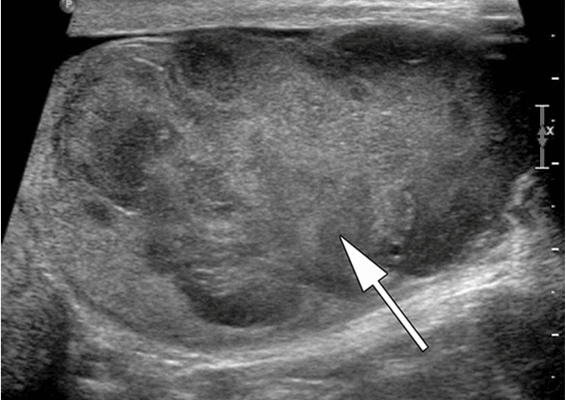

Ультразвуковое исследование (УЗИ) мошонки является предпочтительным начальным визуализирующим исследованием для оценки образования яичка. УЗИ может подтвердить наличие новообразования, определить его расположение и оценить состояние противоположного яичка (рис. 4). Чувствительность метода достаточно высокая - от 92 % до 98 %.

![Снимок УЗИ яичка]()

Снимок УЗИ яичка